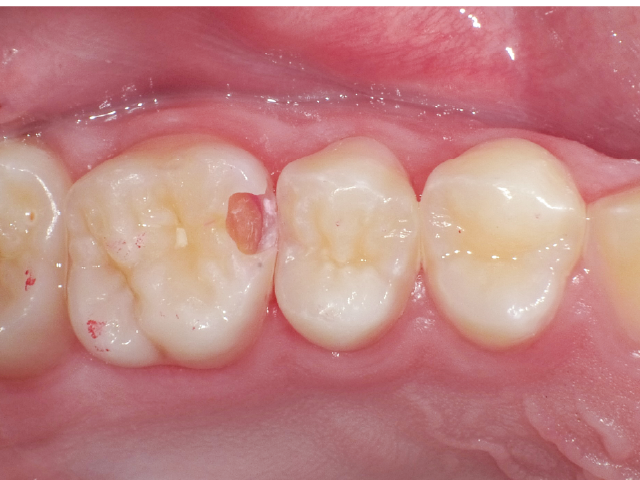

①窩洞形成段階(図1~7)

本症例では、ダイヤモンドの微粒子でコーティングされたエアースケーラーチップを窩洞形態の仕上げに使用。隣在歯の誤切削を防止し、エナメル質の切削断面を歯肉側窩縁までなめらかになるよう仕上げました。

本チップは切削時にストレスが少ない穏やかな振動のエアースケーラー専用のダイヤモンドチップで、切削部となる半球形状の面にのみダイヤモンド砥粒がコーティングされており、背面平坦部は隣在歯を削らないよう平滑になっています(図8、9)。チップの屈曲角度は110°に設定され、窩洞へのアクセスが容易な形状となっています。S67D(アングルの外側)、S68D(アングルの内側)チップは半球状の切削部位が設定され、臼歯部の近遠心両側の窩洞形成に使用が可能です。本症例では、左上6近心隣接面部の窩洞であったため、アングルの外側に半球状の切削部位が設定されている「S67D」を使用しました。これらの器具を使用することにより、頬舌側の隅角部歯質を温存した最小限の規模で窩洞形成を終了、防湿操作および隔壁の設置に移行することができました。